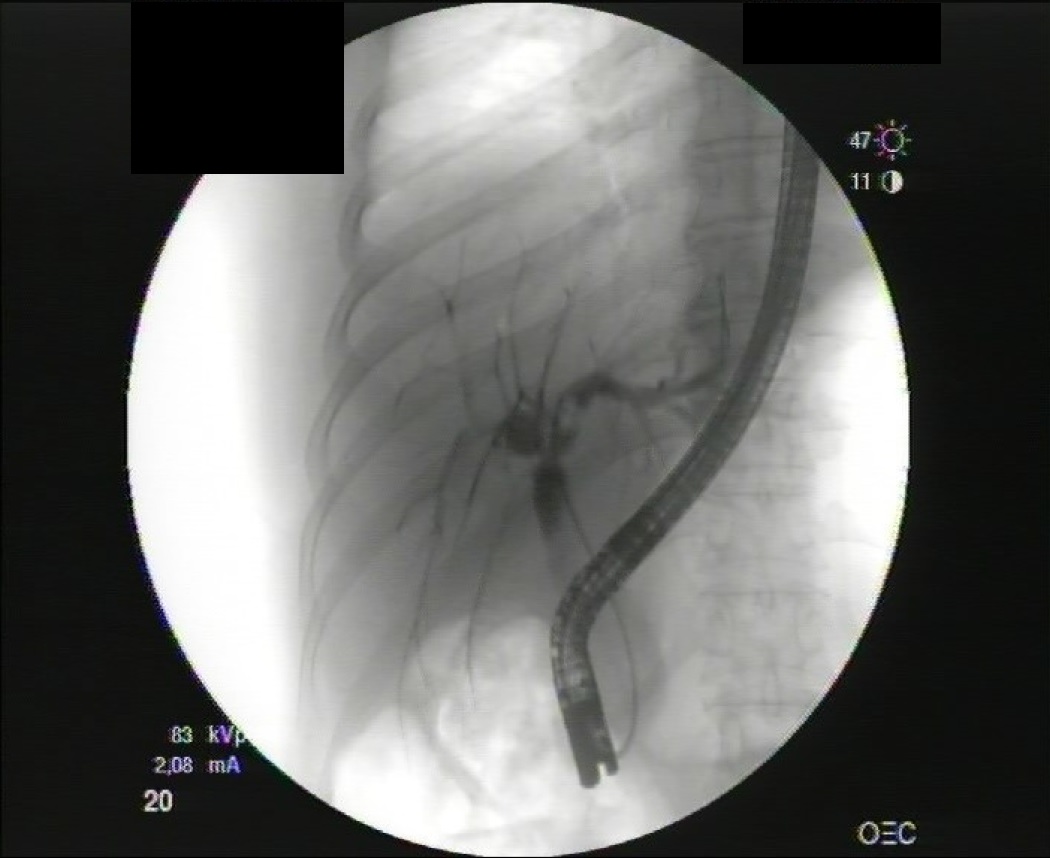

Presentamos el caso de una mujer de mediana edad con antecedentes de colecistectomía y varios episodios de coledocolitiasis residual resueltos endoscópicamente. Acude al servicio de Urgencias por un nuevo cuadro de dolor abdominal y alteración de enzimas hepáticas, apreciándose en las pruebas de imagen lesiones sugestivas de abscesos hepáticos sin poder descartarse un origen maligno. Dada esta duda se decide realizar una biopsia con aguja gruesa llegando al diagnóstico de pseudotumor inflamatorio hepático relacionada con la enfermedad por IgG4. Ésta es una entidad infrecuente pero que debe ser tenida en cuenta debido a que, a diferencia de la patología maligna, que es el principal diagnóstico diferencial, su comportamiento es benigno, con buena evolución con tratamiento médico. Por ello es vital un adecuado diagnóstico para evitar procedimientos diagnóstico-terapéuticos agresivos.